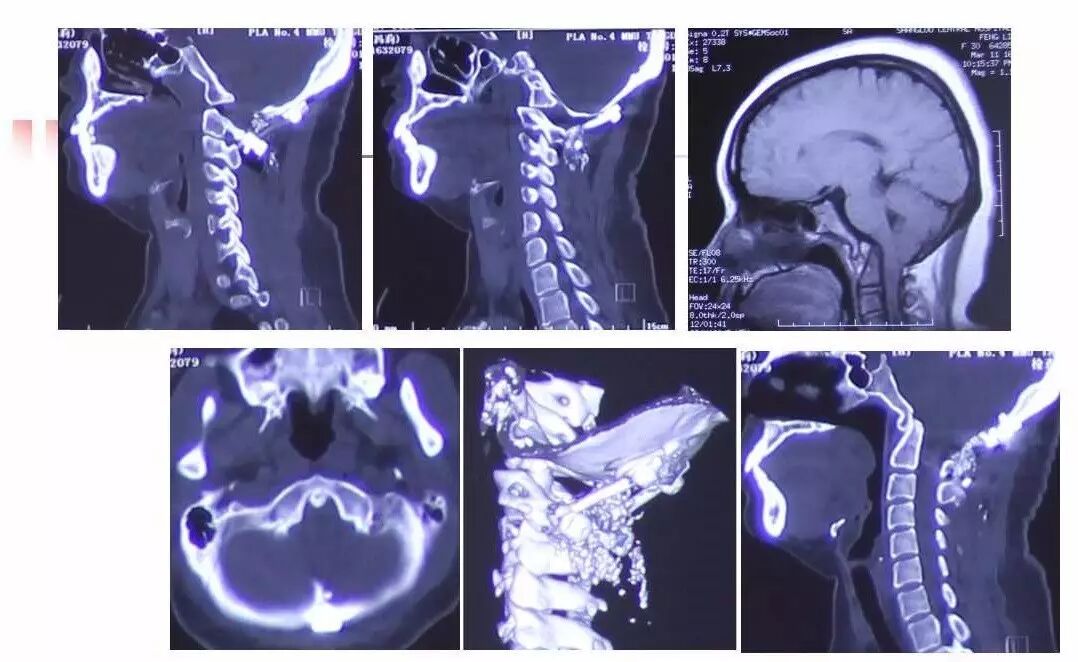

在脊柱神经外科、显微神经外科和颅底肿瘤外科前沿研究和临床诊治领域有着扎实的基础,为全国首批获得脊柱神经外科医师培训认证的神经外科医生。擅长颈椎病、椎管肿瘤及各种脊柱疑难疾病的诊治、脑肿瘤微创手术,尤其擅长颈椎退行性疾病的手术,率先在国内开展了颅底凹陷后路复位、颈前路减压融合等高难度手术,多年来收治了来自全国各地的大量患者,疗效达到国内领先水平。